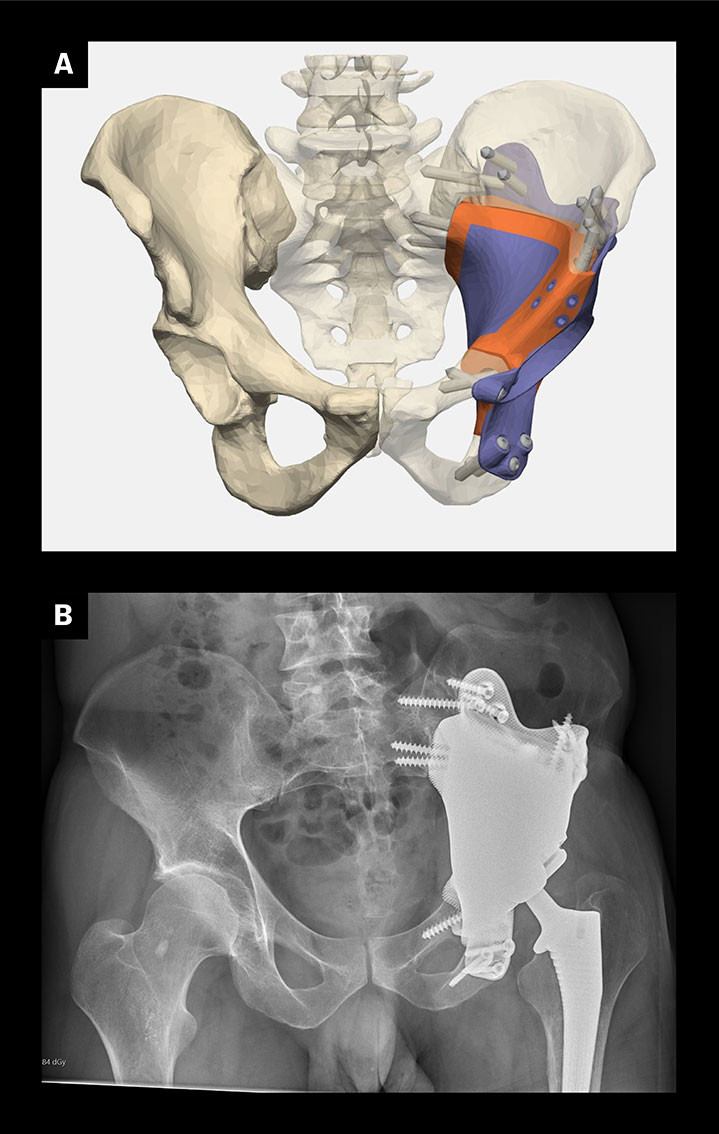

Moderne billeddiagnostikk kan nøyaktig beregne beindefekter etter kreftkirurgi, misdannelser og skader. Titanimplantater kan skreddersys til pasientenes anatomi, erstatte og perfekt tilpasses beintapet. Implantatet produseres ved bruk av 3D-printing og overflatebehandles, hvoretter det forankres i gjenværende bein rundt defekten i skjelettet (figur 3). Dette kan blant annet gi gangfunksjon etter bekkentumorfjerning, erstatte skalledefekter, gi ansiktsform og bedring av tyggefunksjon (20, 21).